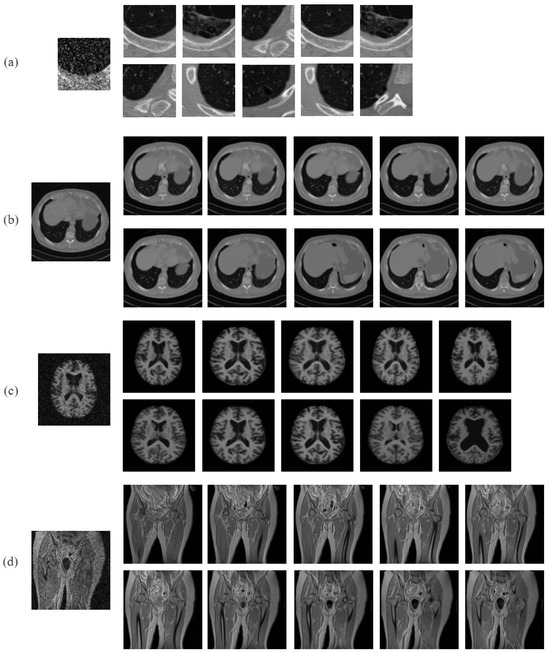

4.2. Performance Analysis on Noisy Images

3.3. Dataset Description